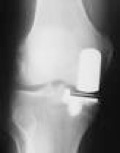

X-Ray showing Oxford Partial Knee Replacement

X-Ray of a medial Oxford Uni-compartmental Knee Replacement